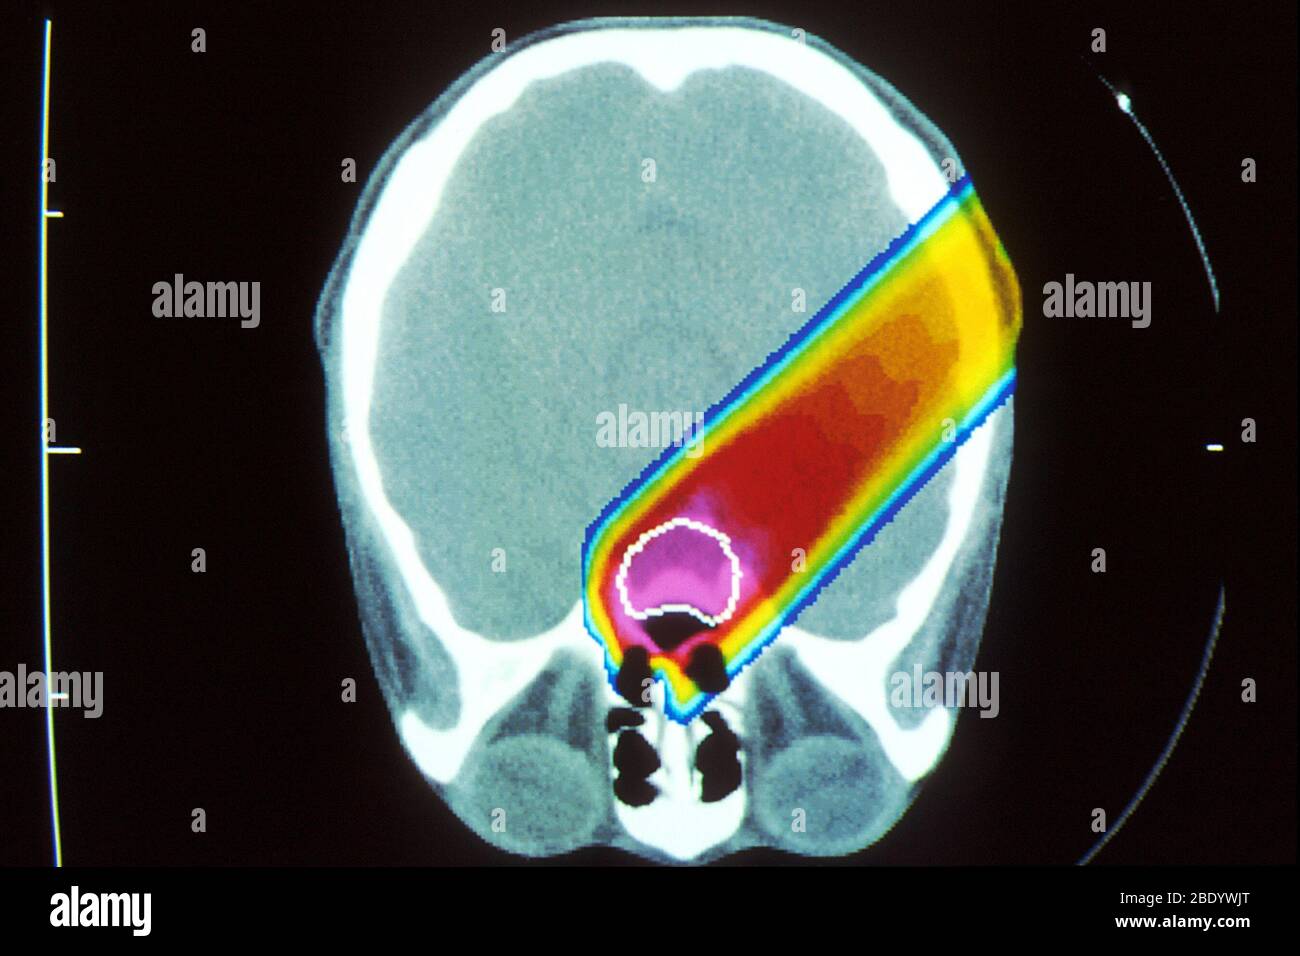

Faisceau de protons du cerveau pendant l'acquisition CT Banque D'Imageshttps://www.alamyimages.fr/image-license-details/?v=1https://www.alamyimages.fr/faisceau-de-protons-du-cerveau-pendant-l-acquisition-ct-image352810717.html

Faisceau de protons du cerveau pendant l'acquisition CT Banque D'Imageshttps://www.alamyimages.fr/image-license-details/?v=1https://www.alamyimages.fr/faisceau-de-protons-du-cerveau-pendant-l-acquisition-ct-image352810717.htmlRM2BDYWJN–Faisceau de protons du cerveau pendant l'acquisition CT

Faisceau de protons du cerveau pendant l'acquisition CT Banque D'Imageshttps://www.alamyimages.fr/image-license-details/?v=1https://www.alamyimages.fr/faisceau-de-protons-du-cerveau-pendant-l-acquisition-ct-image352810720.html

Faisceau de protons du cerveau pendant l'acquisition CT Banque D'Imageshttps://www.alamyimages.fr/image-license-details/?v=1https://www.alamyimages.fr/faisceau-de-protons-du-cerveau-pendant-l-acquisition-ct-image352810720.htmlRM2BDYWJT–Faisceau de protons du cerveau pendant l'acquisition CT

Protonthérapie Banque D'Imageshttps://www.alamyimages.fr/image-license-details/?v=1https://www.alamyimages.fr/protontherapie-image352810757.html

Protonthérapie Banque D'Imageshttps://www.alamyimages.fr/image-license-details/?v=1https://www.alamyimages.fr/protontherapie-image352810757.htmlRM2BDYWM5–Protonthérapie